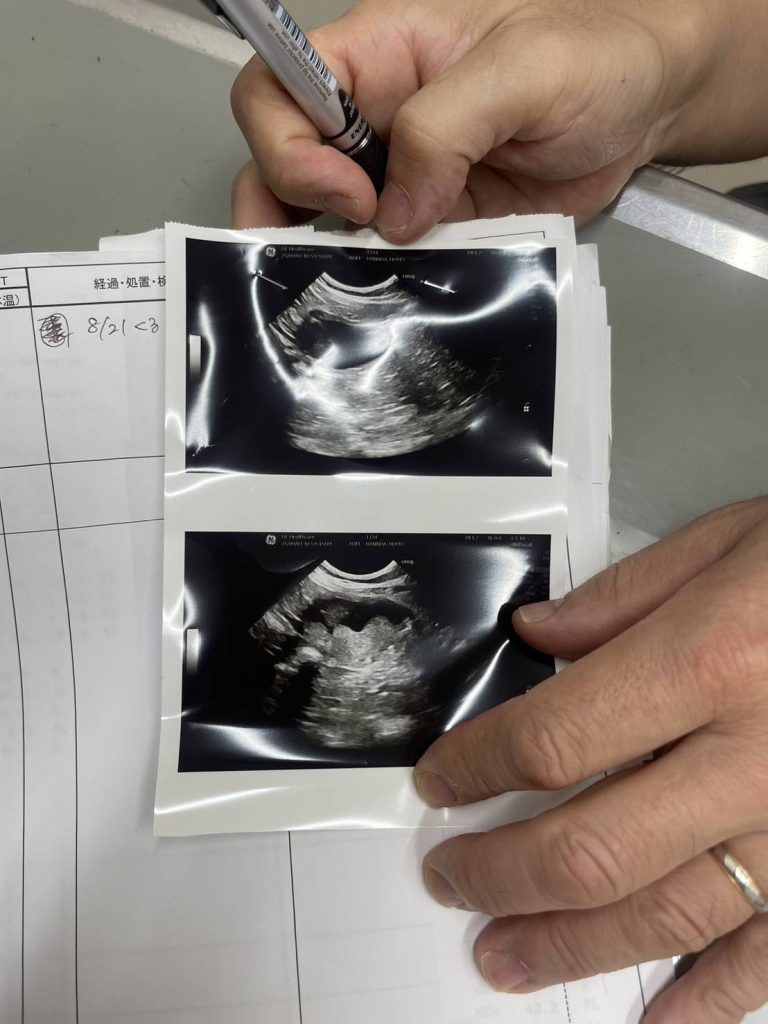

上記の写真は、娘が飼っている猫の膀胱癌の腫瘍画像です。